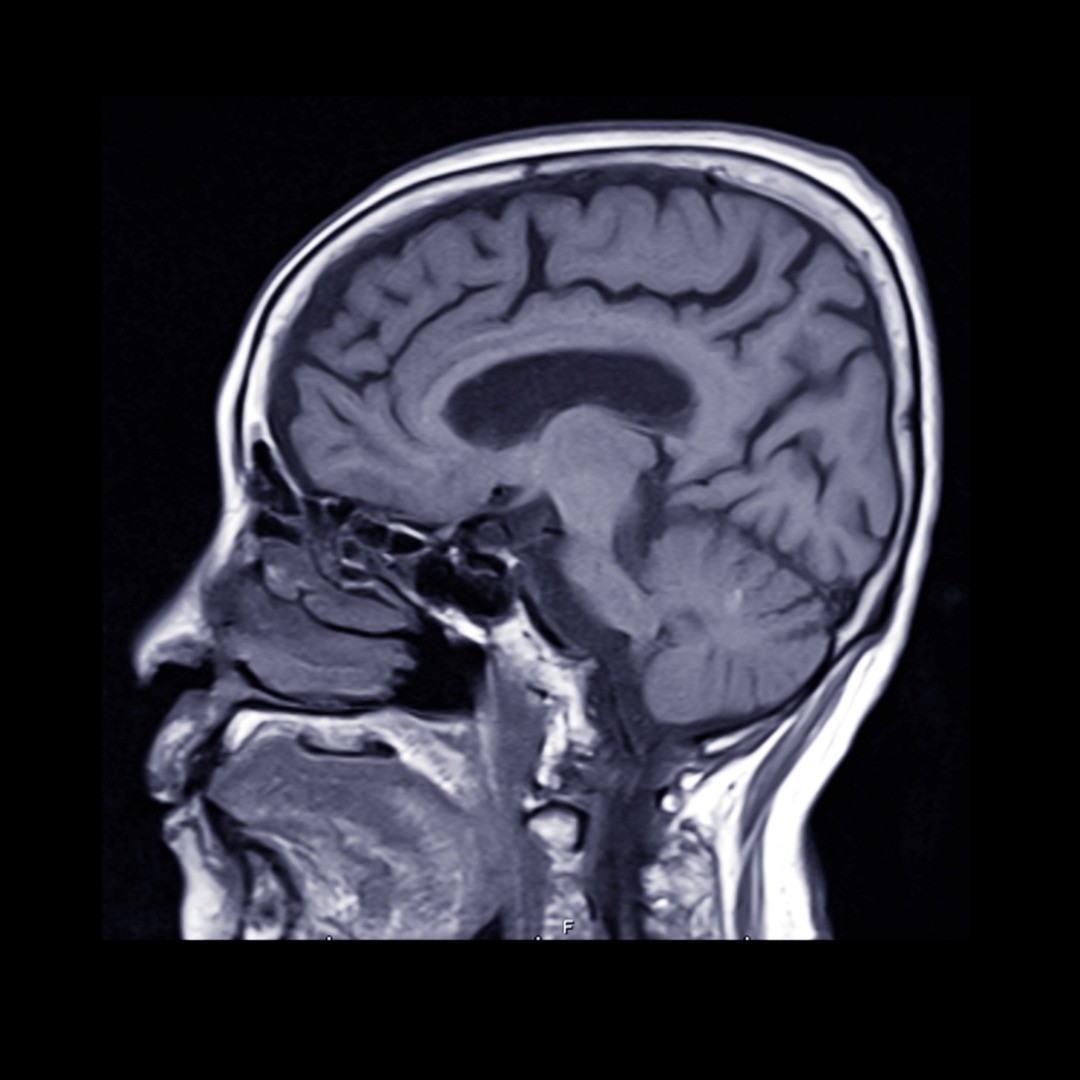

Cerebral aneurysm treatments depend on a variety of factors: whether the aneurysm, a bulge in the wall of the artery, is pre-rupture or after an event, your health and age, how small or large the aneurysm is, and whether it is causing neurological symptoms among other risk factors.

Aneurysm Clipping – In this brain aneurysm treatment, a neurosurgeon places a small surgical clip around the base of an intracranial aneurysm, blocking off the flow of blood to the aneurysm and limiting the likelihood of it bursting. Surgical clipping is a long-established medical procedure for treating both ruptured and pre-ruptured aneurysms.

Surgical Clipping – During this surgical procedure, a tiny clip is attached to the base of the aneurysm to prevent blood flow— thereby decreasing the likelihood of it bursting or rupturing if it’s pre-rupture or to treat a ruptured aneurysm. To reach the aneurysm, the neurosurgeon performs a small craniotomy, which temporarily removes a portion of the skull, and an incision in the brain covering called the dura mater allows the surgeon to carefully retract the brain and trace the affected artery to the aneurysm. Once there, the clip is placed on the neck of the aneurysm.